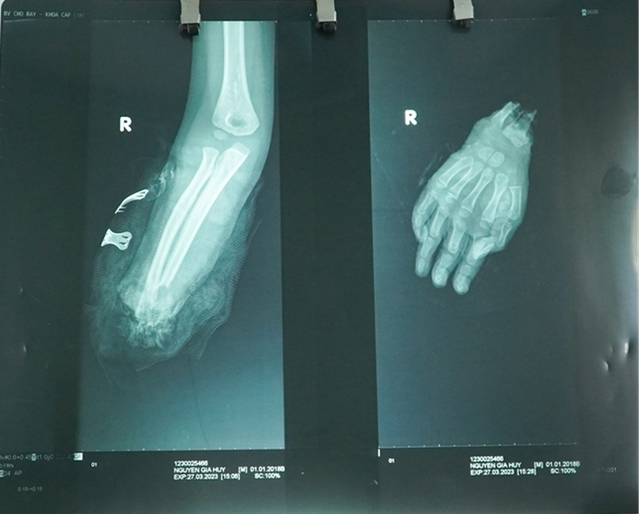

| Phim chụp X-quang cánh tay bị đứt lìa của bệnh nhi H. |

Người nà bệnh nhi cho biết, bé đang đi bộ thì bị xe gắn máy đụng phải dẫn đến đứt lìa bàn tay phải. Sau khi sơ cứu tại địa phương, bé được chuyển đến cấp cứu tại Bệnh viện Chợ Rẫy.

Theo BS CK1 Nguyễn Phước Bình, Khoa Chấn thương chỉnh hình, tại Bệnh viện Chợ Rẫy, bệnh nhân đã được phẫu thuật cấp cứu (với sự tăng cường của đội ngũ bác sĩ về vi phẫu) nối lại bàn tay đứt rời, nối lại xương, mạch máu, gân, cơ, dây thần kinh bàn tay…